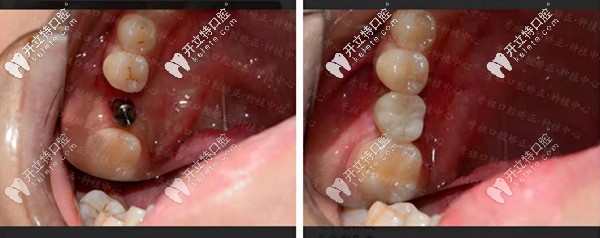

【種植牙案例一】單顆種植牙修復,還原咬合力!

長沙牙祖口腔周磊種植案例一

顧客情況:女性,19歲,右下6號牙殘根不能保留。

種植方案:拔除殘根牙后做種植處理。

種植周期:3個月